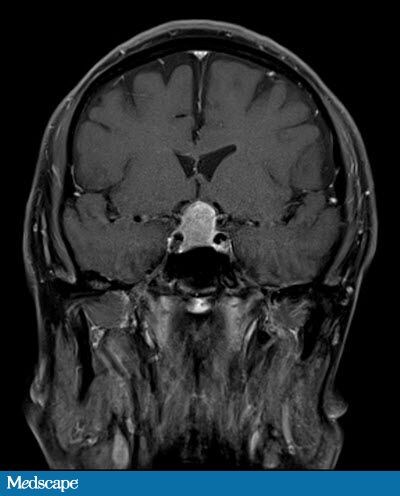

31+ Mri Brain Scan Results White Spots PNG. A brain lesion appears as a dark or light spot that does not look like normal brain tissues. The images produced allow doctors to see lesions in your cns.

Lesions show up as white or dark spots, depending on the type of damage and the your doctor may also recommend additional mri scans of the brain, the spine, or both at certain intervals to monitor disease activity and progression. A brain mri scan can show if a stroke has occurred. Does someone know what may it be?